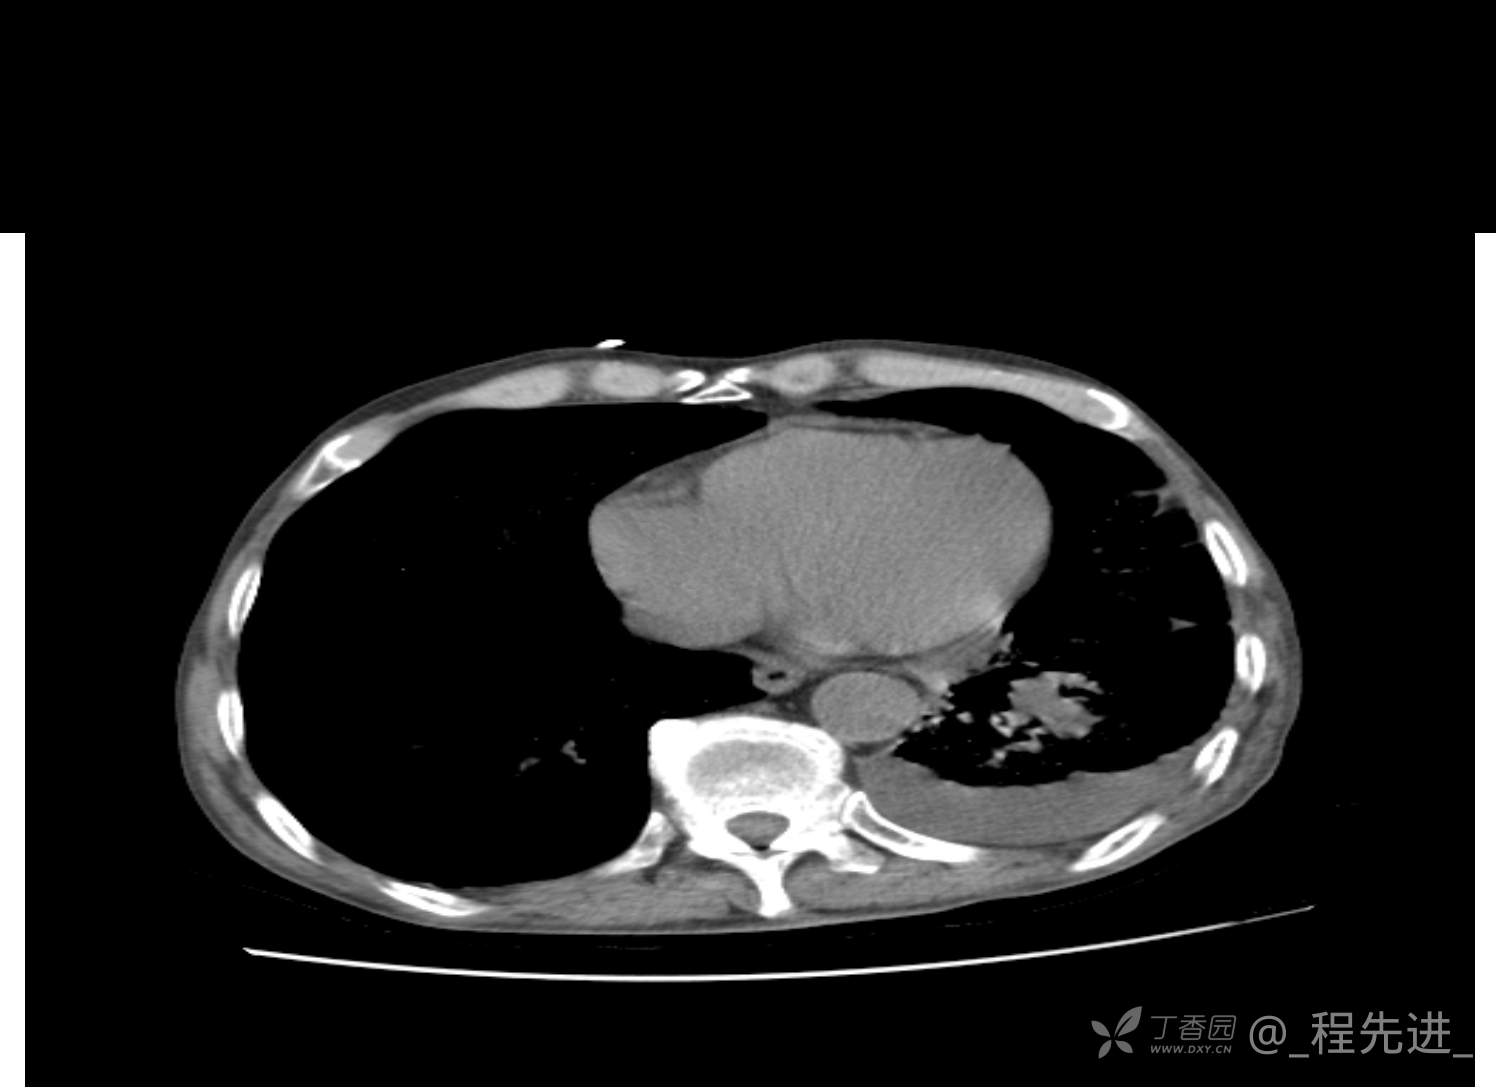

患者性别:男

患者年龄:81岁

简要病史:反复咳嗽、咳痰20余年,加重1周。两肺呼吸音低,可闻及散在干湿啰音。